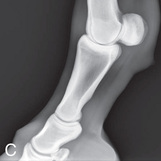

The distal phalanx and the navicular bone comprise the digit or foot. Common indications for imaging the equine foot include localized lameness by clinical examination (pain on pressure from foot testers, increased digital pulses, etc.) or by diagnostic analgesia, laminitis, penetrating wounds, or as required for a prepurchase examination.1

The lateromedial view of the pastern provides information on the integrity of the foot axis and the bones and joints in the digit.

| Lateral (Standard) (Fig. 24.62D) | Lateromedial | On a block to elevate limb for P-III; resting on ground for other views. | 90 degrees lateral to MSP, parallel to ground on area of interest: coronary band for PIII | |